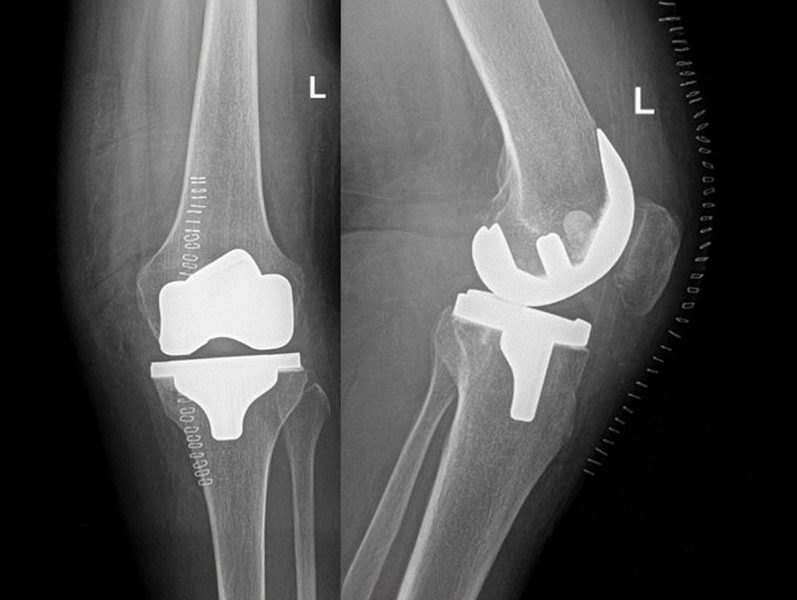

In unserer Abteilung werden primäre und Revisionsendoprothesen an Hüft –, Knie – und Schultergelenken durchgeführt.